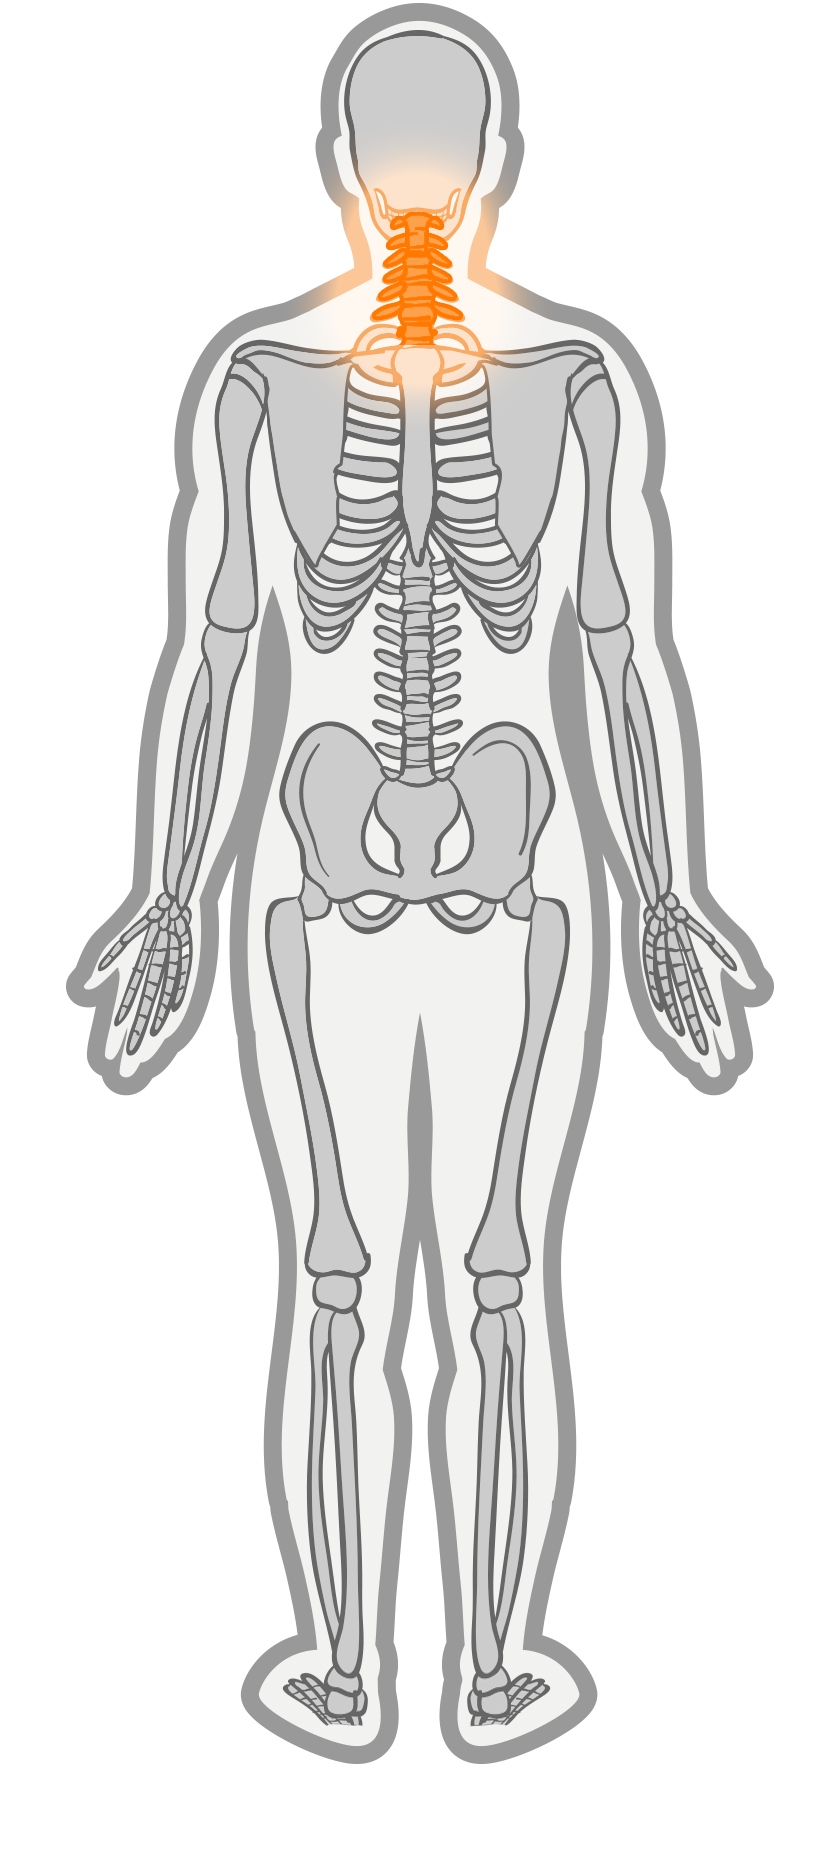

Een whiplash wordt meestal veroorzaakt door een auto-ongeluk waarbij het slachtoffer van achteren of van opzij wordt aangereden. Bij een aanrijding van achteren worden de rug en schouders naar voor geduwd, terwijl het hoofd achterblijft. Het hoofd van de inzittende krijgt daardoor eerst een krachtige slag naar achteren en daarna naar voren, op het moment dat de aangereden auto tot stilstand komt.

Deze bewegingen gaan met veel snelheid en kracht gepaard. Hierdoor kunnen er door uitrekking, compressie en verschuiving (micro)letsels ontstaan van allerlei structuren in het lichaam, vooral in nek en schedel. Als op het moment van het ongeval het hoofd gedraaid was, is de kans op letsel nog groter. Een whiplash ontstaat niet alleen bij auto-ongelukken maar ook ontstaan tijdens het sporten of thuis.

Er is een hele lijst met klachten waarmee een whiplashpatiënt te maken kan krijgen. Hoofd- en nekpijn, maar ook spierzwakte in schouders en nek en vreemde gevoelssensaties, zoals tintelingen in de handen, evenwichtsstoornissen en concentratiestoornissen.